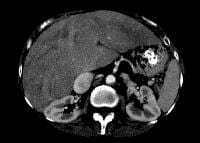

Decompensated right ventricular or biventricular heart failure causes transmission of elevated right atrial pressure to the liver via the inferior vena cava and hepatic veins. At a cellular level, venous congestion impedes efficient drainage of sinusoidal blood flow into terminal hepatic venules. Sinusoidal stasis results in accumulation of deoxygenated blood, parenchymal atrophy, necrosis, collagen deposition, and, ultimately, fibrosis.